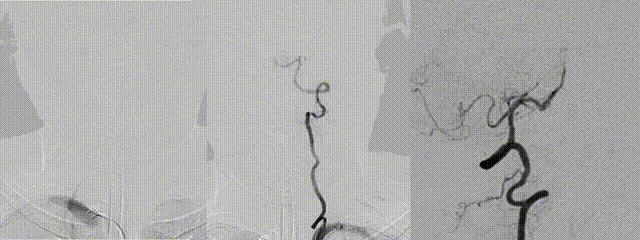

3D DSA evaluation: Poor hemodynamic compensation at the lesion segment. Balloon dilation was considered risky due to inaccessibility and high risk of vessel rupture. Microcatheter was re-advanced across the stenosis. A 3.0 mm × 15 mm non-tapered intracranial stent was deployed slowly.

The stent expanded and apposed well, with good in-stent flow and improved visualization of distal branches.

15-minute follow-up angiography showed stable in-stent flow in the basilar artery